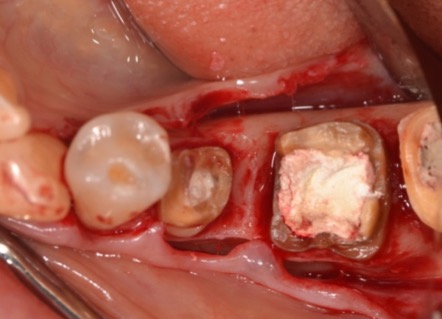

歯周組織再生療法の術前の様子です。

歯肉を切って、中をきれいにしていくと、根尖近くまで骨がなくなっていることが分かります。

歯周組織再生療法を行います。